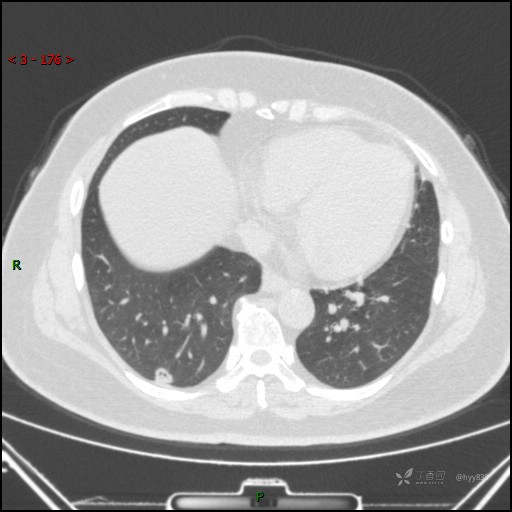

51岁/F,体检发现肺结节,又见“鬼脸”,增强也有特点,请分析---结果公布~

简要病史:体检发现右下肺结节,来我院行进一步增强检查并手术

胸部CT平扫